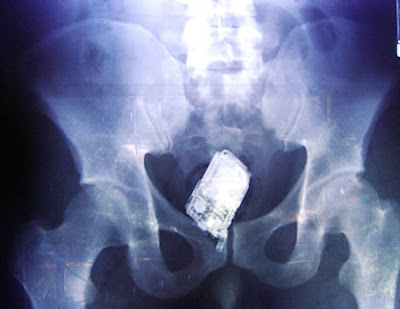

The Most Bizarre X-Rays

This X-ray reveals a cell phone lodged in a Salvadoran prisoner's lower intestine. According to news reports, the man is one of four prisoners who are members of the Mara Salvatrucha street gang. The men were caught with cell phones, spare chips and a charger that they had attempted to smuggle, according to authorities at San Salvador's Zacatecoluca prison.